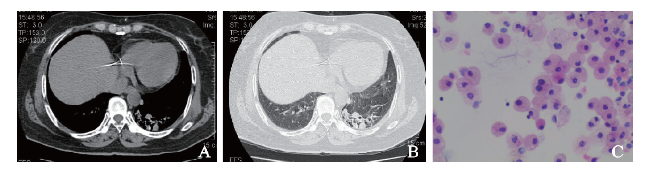

例3 患者女,59岁。因头晕6个月,头痛10余日于2017年5月13日在我院神经内科就诊。6个月余前患者无明显诱因出现发作性眩晕,体位变化时明显,10余日前出现头痛、头晕伴恶心、呕吐胃内容物多次,偶有喷射样呕吐,头痛较剧烈,以前额为主,休息后可缓解,头痛时伴视物模糊、眼前发黑感,9 d前曾出现头痛时意识障碍、大小便失禁并出现发热,体温最高38℃,当地医院查头颅MRI/磁共振血管成像(MRA)未见明显异常,胸部X线片示左肺下叶感染,予抗感染、止痛、退热等治疗后未再发热,仍反复头痛、头晕,伴恶心、呕吐,体质量近1月下降约3 kg。既往有乙型肝炎史,个人史无特殊。入院体格检查:体温:36.8℃,脉搏82次/分,呼吸18次/分,血压142/78 mm Hg。神清,对答切题,双侧瞳孔等大、等圆,直径约3 mm,远视力变差,对光反射灵敏,可见水平眼震,伸舌居中,鼻唇沟无变浅,躯干四肢深浅感觉无明显异常,四肢肌力、肌张力正常,颈项强直,克尼格征(+),双侧巴宾斯基征可疑阳性。入院后完善检查,血常规示:血红蛋白127 g/L,白细胞9.18×109/L,血小板30×109/L;脑脊液涂片示隐球菌1 982 /ml;脑脊液生化常规示糖 2.59 mmol/L,氯115.4 mmol/L,脑脊液蛋白0.62 g/L,白细胞计数14×106/L,无色、透明、清亮、无薄膜形成,球蛋白定性(+),红细胞24×106/L。10月18日胸部CT示:①左肺下叶基底段病变,考虑真菌感染;②双肺少许炎症,左肺下叶基底段见多发斑片状、结节状实变影,边界不清,内部密度不均,内可见结节状高密度阴影,病灶较前稍减少(图3A、B),余双肺见少许斑片状稍高密度影。肺部病灶抗感染治疗后于11月10日复查CT,结果示较前进展,遂完善纤支镜检查,12月14日BAL涂片及液基细胞学示较多泡沫样细胞及少量上皮细胞、淋巴细胞,未见确切癌细胞(图3C)。特殊染色结果:PAS(-),抗酸染色(-),六氨银(-)。长期使用伏立康唑联合氟胞嘧啶抗感染治疗后复查CT好转。

图3 例3肺隐球菌感染患者的胸部CT及BAL涂片结果

A:胸部CT纵隔窗;B:胸部CT肺窗;C:BAL涂片(HE染色,×400)